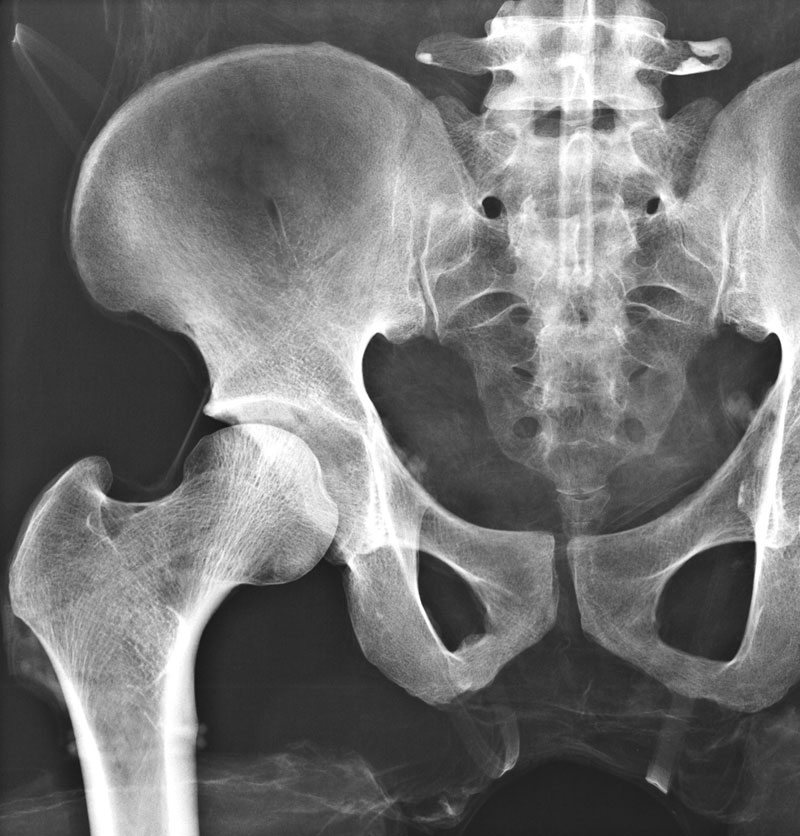

Dieses weltweit einmalige Phantom bietet erstklassige Übungsmöglichkeiten für die Lagerungs- und Einstelltechnik in der Projektions-Radiographie und gehört eigentlich zur Grundausstattung jeder Röntgen-Ausbildungsstätte. Das Phantom enthält ein natürliches menschliches Skelett sowie die Umrisse von Kehlkopf, Lunge, Herz und Nieren (Organe erscheinen als Schatten auf den Röntgenbildern), dadurch können mit dem Phantom echte Röntgenaufnahmen wie beim Patienten gemacht werden. Durch die Verwendung des echten Skeletts können Leitstrukturen im Knochen erkannt werden, was bei Kunststoffskeletten nicht möglich ist. Bei der Montage des Phantoms wird besonderer Wert auf die Darstellung der Gelenkspalte gelegt. Die Gelenke sind voll beweglich montiert, und ermöglichen die Lagerung in den normalen Röntgenpositionen (z.B. Froschposition, Pro- und Supination des Unterarms). Die Arme können nach oben bewegt werden, so dass das Modell auch für alle knöchernen Untersuchungen im CT verwendet werden kann. Bei jedem Phantom handelt es sich um ein handgefertigtes Unikat, welches sich in Größe und Ausführung unterscheiden kann. Je nach Modell können pathologische Befunde vorhanden sein, die äußere Erscheinung kann sich je nach Größe des Modells unterscheiden. Die neue Ausführung dieses Modells wurde in Zusammenarbeit mit einer namhaften deutschen Schule für Med. Techn. Radiologieassistenten komplett überarbeitet und erfüllt alle Anforderungen für die Ausbildung. Der Verkauf dieses Phantoms erfolgt nur gegen Nachweis der medizinischen Verwendung. Natürliche Größe.